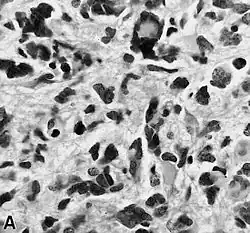

Examen microscópico

El glioblastoma es una neoplasia anaplásica de la glía compuesta por células tumorales astrocíticas pobremente diferenciadas, polimórficas, con marcadas atipias nucleares y una intensa actividad mitótica. Otras características peculiares a fines diagnósticos son también la marcada proliferación microvascular y la presencia de necrosis. Como sugiere el adjetivo "multiforme", la morfología histológica del glioblastoma es extremadamente variable, con células redondeadas, en forma de huso, de dimensiones más bien pequeñas o muy grandes. Mientras que algunos glioblastomas muestran un alto grado de polimorfismo celular y nuclear, con numerosas células gigantes plurinucleadas, otros presentan una conformación caracterizada por una celularidad intensa, pero más bien repetitiva.

La naturaleza astrocítica de la neoplasia puede resultar bastante fácil de identificar, al menos localmente, en algunos tumores, pero difícil de reconocer en otros, debido al alto grado de anaplasia. La heterogeneidad de región a región del glioblastoma es relevante y dificulta el diagnóstico en muestras limitadas, como las obtenidas por biopsia estereotáxica[70] (véase la fotografía en Cirugía). A pesar de la presencia predominante de células poco diferenciadas, en algunos puntos se pueden distinguir astrocitos neoplásicos más diferenciados. Esto es particularmente cierto en los casos de glioblastoma como resultado de la progresión de un astrocitoma difuso (grado II de la escala OMS). La transición entre zonas que aún poseen diferenciación astrocítica reconocible y zonas de alta anaplasia celular puede ser continua o repentina. Un cambio brusco en la morfología refleja habitualmente la aparición de un tumor diferente, fruto de la adquisición de una o más alteraciones genéticas adicionales.[71]

En el contexto de la neoplasia se observan grandes áreas de necrosis, rodeadas de núcleos dispuestos paralelos entre sí, formando "empalizadas" típicas. Se encuentra una marcada proliferación de células endoteliales con formación de numerosos vasos, a veces con apariencia de montón o madeja. Algunos tienen pared hialina y otros están trombosados. La proliferación endotelial, sin embargo, no es difusa sino focalizada en algunos puntos. Alrededor de la neoplasia se pueden encontrar zonas de astrocitos gemistocíticos (astrocitomas difusos de grado II).[11][61]